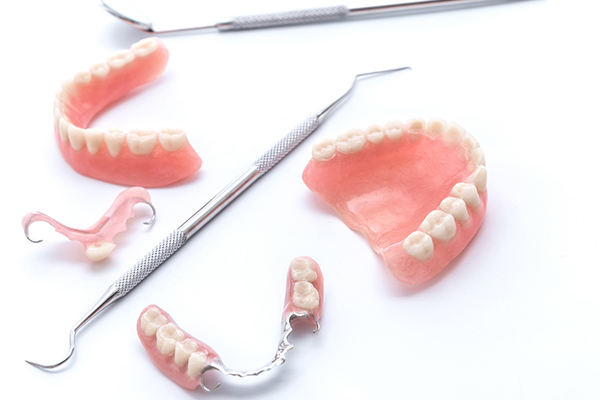

インプラントとは、体内に埋め込む医療機器や材料の総称で、⻭がなくなった場合に、顎骨に埋め込む人工⻭根もインプラントの一つです。事故や⻭槽膿漏、虫⻭などで⻭を失った方や、先天的に⻭がない方など、⻭がない部位の顎の骨にインプラントを埋め、その部位に⻭を付ける治療法をインプラント治療と言います。インプラント治療は、1本の⻭がなくなった場合から全部の⻭がなくなった場合まで適用できる治療方法です。